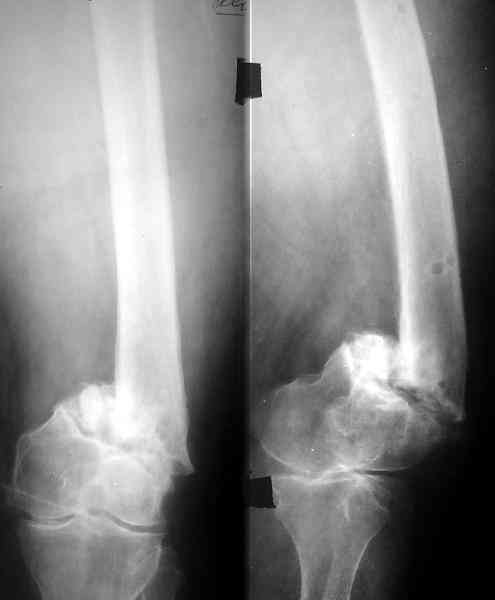

По всей вероятности, после перелома бедренной кости, случившегося 15 лет назад, у больной сформировался псевдоартроз в дистальной эпиметафизарной зоне. Травма этого года привела, с моей точки зрения, к частичному разрушению псевдоартроза, а не к повторному перелому. Учитывая амнестические данные о больной, я бы не спешил с оперативным вмешательством, а предложил бы больной съёмный ортез и нагрузку на ногу в течение двух-трёх месяцев. Такой промежуток времени при данной патологии не ухудшит условия для оперативного вмешательства, если оно потребуется, но позволит более определённо установить необходимость такового, если конечность не станет опорной или больная сама станет настаивать на оперативном вмешательстве.

Пример подобного ложного сустава в приложении.